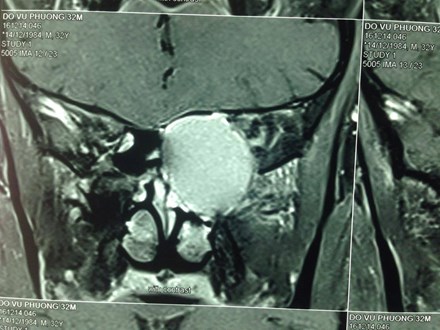

Hình ảnh khối u nhầy chèn ép thần kinh thị giác. Ảnh: Lao Động |

Kết quả chụp CT cắt lớp, các bác sĩ phát hiện bệnh nhân có khối u nhầy vùng sàng sau tủy xương và chèn ép thần kinh thị giác, đây chính là nguyên nhân gây mù mắt.